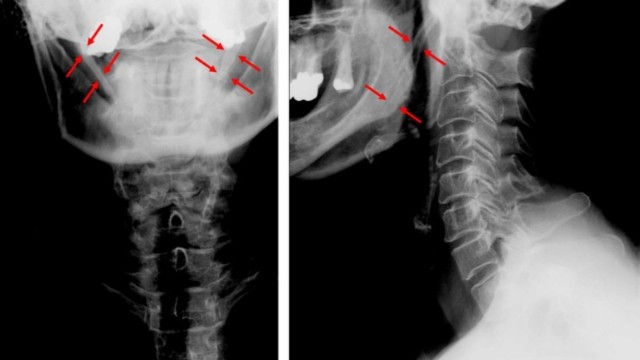

Mỏm trâm là một xương sụn hình trụ, dài nằm trên xương thái dương mà ít người biết đến. Hãy cùng tìm hiểu xem dài mỏm trâm biểu hiện thành những triệu chứng nào qua bài viết sau.